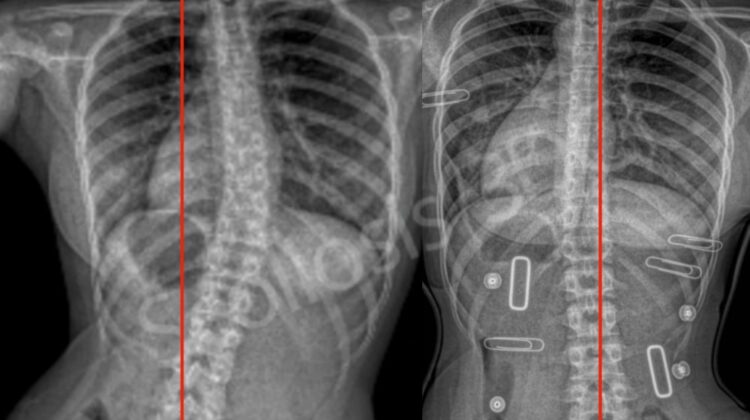

يختلف الهدف من التصحيح حسب العمر، نوع الانحناء، درجة الاعوجاج، ونوع الحزام المستخدم. ومع ذلك، هناك نسب تمثل “المعيار الذهبي” التي يسعى إليها الأطباء:

1. التصحيح المثالي: 50% أو أكثر

هذه النسبة تعتبر الأفضل، وتشير إلى أن الحزام يعمل بكفاءة عالية وأن تصميمه مناسب تمامًا لانحناء الطفل.

وتُلاحظ هذه النسبة عادة في:

الانحناءات المرنة

الأطفال الأصغر سنًا

عند استخدام أحزمة ثلاثية الأبعاد مصممة بشكل فردي (3D brace)

2. التصحيح الجيد: 30% – 50%

هذه النسبة مقبولة طبيًا وتُعد مؤشرًا جيدًا على فعالية الحزام، خصوصًا إذا كانت زاوية الاعوجاج متوسطة (من 20 إلى 40 درجة).

مع المتابعة الجيدة والالتزام بعدد ساعات الارتداء، بالتالي يمكن أن تمنع هذه النسبة تطور الانحناء.

3. التصحيح الضعيف: أقل من 30%

هذه النسبة تشير عادة إلى وجود مشكلة في:

مواضع وسادات الضغط

مقاسات الحزام

التزام الطفل بحسن الارتداء

وفي هذه الحالة يجب مراجعة الطبيب أو المركز المختص لإعادة ضبط الحزام.

يتم تقييم الأشعة عادة كل 4 إلى 6 أشهر، وليس بشكل متكرر، لأن التغيّرات تحتاج وقتًا لتظهر.